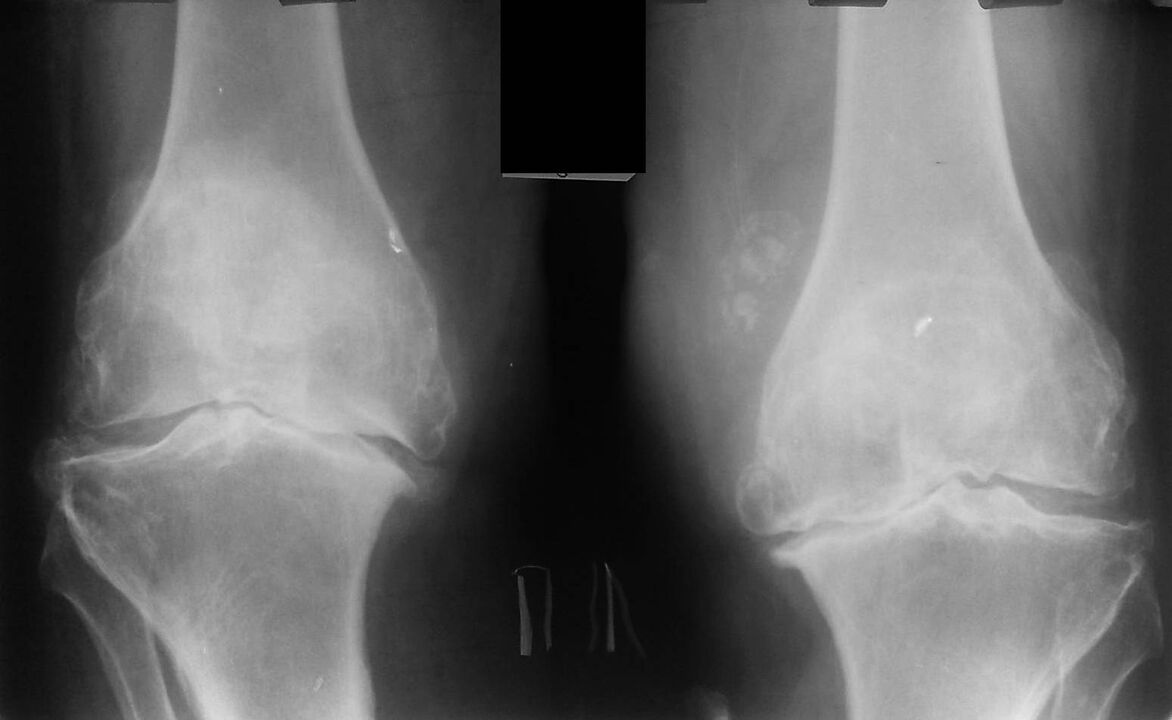

This diagnosis is made on the basis of patient complaints, examination data, palpation of the diseased joint and x-ray examination.

X-ray is a standard research method that allows you to confirm the diagnosis, determine the degree of pathological changes, monitor the dynamics of the process and exclude other pathological processes (for example, tumors) in the tibia and femur .

It should be noted that the primary changes in the structures of the knee joint may be absent on radiographs. The narrowing of the joint space and the compression of the subchondral zone are then determined. The articular ends of the femur, and especially the tibia, expand, the edges of the condyles become pointed.

Auxiliary diagnostic methods are CT (computed tomography) and MRI (magnetic resonance imaging), which allow a more detailed study of pathological changes in bone structures and detect changes in soft tissues.